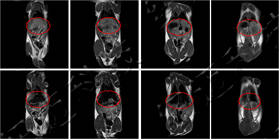

大鼠造影前后MRI冠状面

仪器使用小动物核磁共振成像系统,图像为T1加权像横断面、冠状面,采样参数如下:FOV=100mm×100mm, TR=400ms, TE=19ms, 层厚3.5mm, 层间距1mm, 累加次数16, K空间大小192×256。成像结果显示,注射造影剂后,大鼠心脏与肝脏变亮,且随代谢时间延长逐渐变暗。